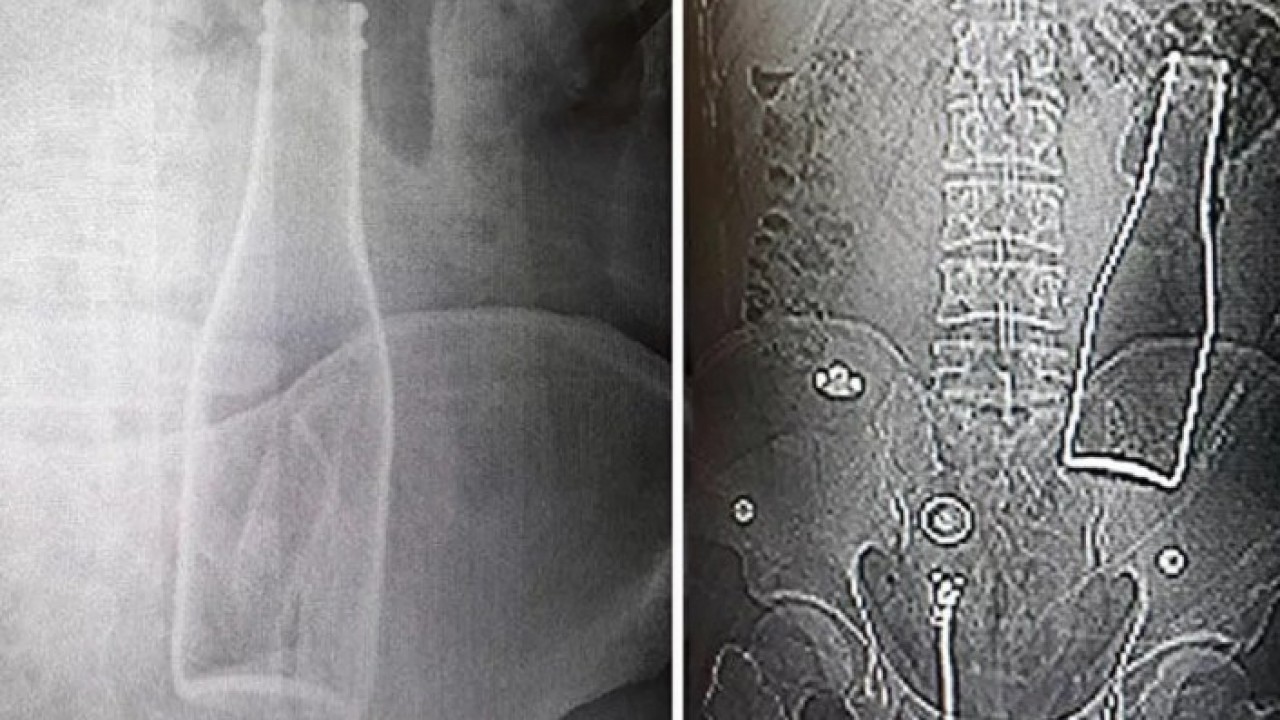

Bunun üzerine röntgen filmi çekilen gencin kalın bağırsağında şişe olduğu görüldü. Makattan girdiği belirlenen şişe, yaklaşık bir saat süren ameliyatla çıkarıldı.